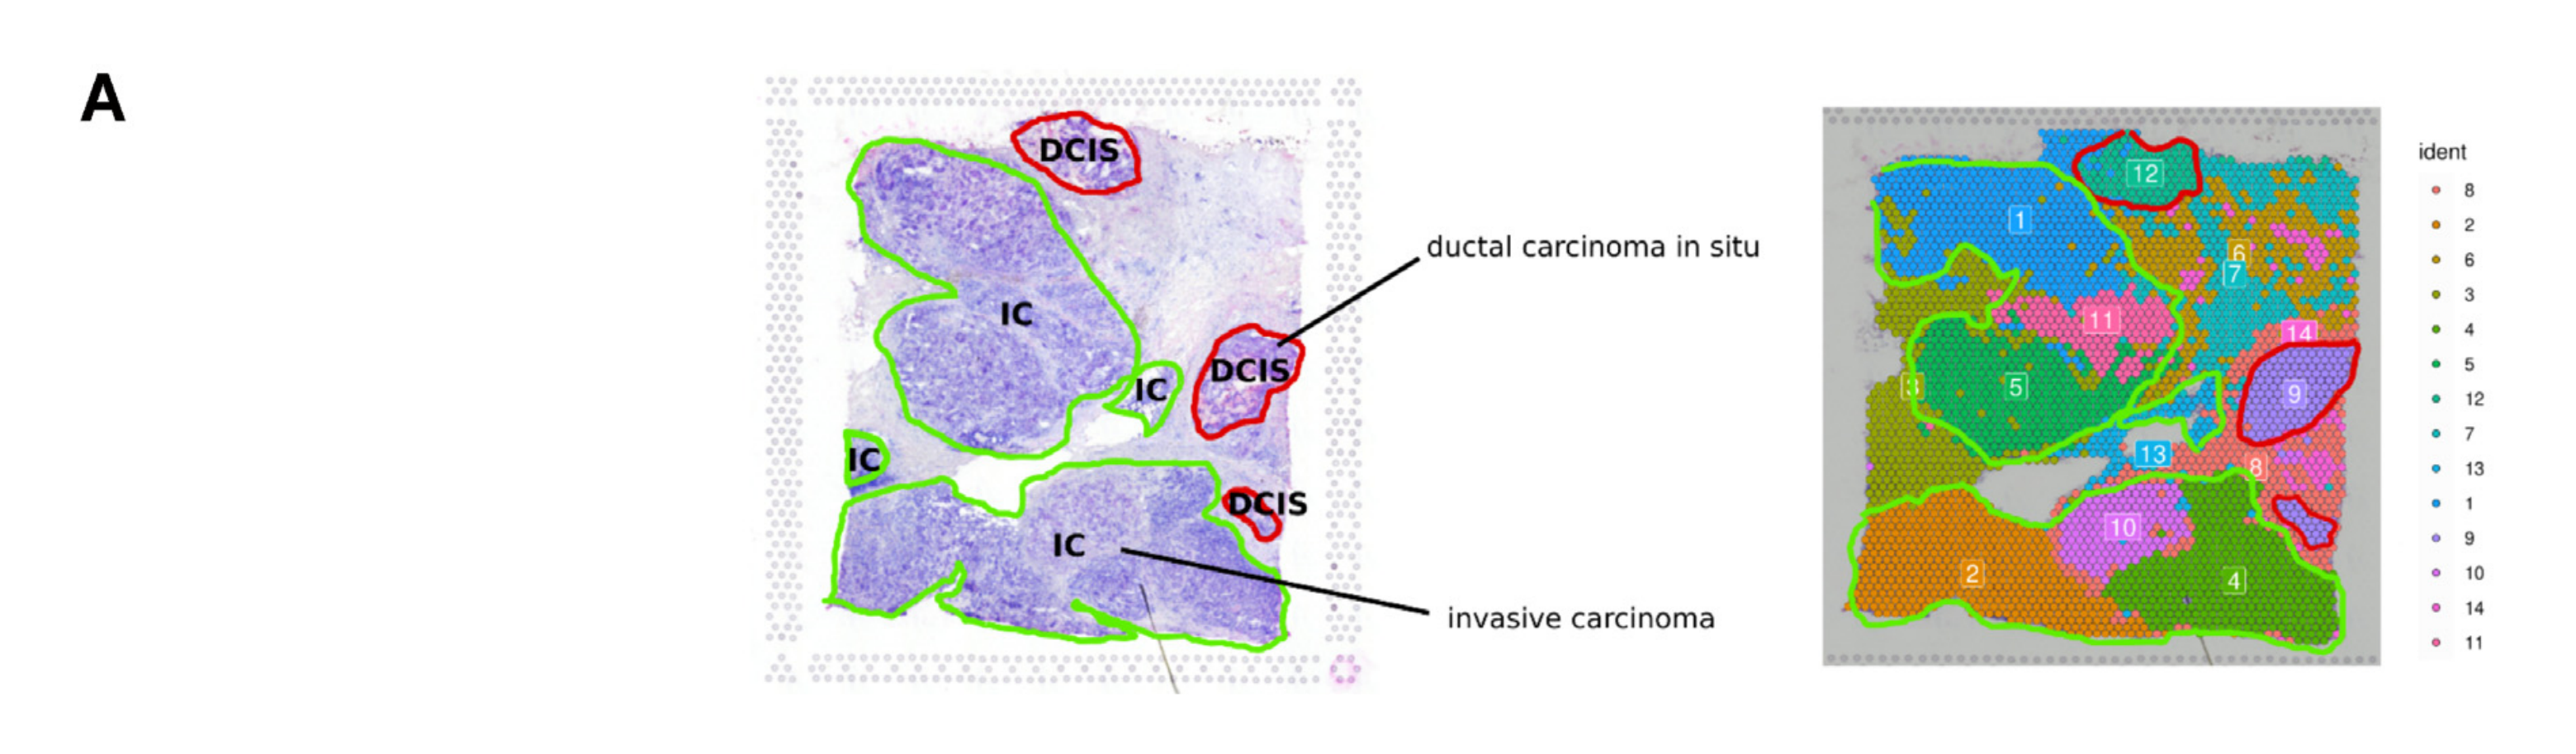

What is the spatial distribution of disease subtypes?

What is the tissue morphology and architecture?

Where are tumor regions located within the spatial architecture of a tissue section?